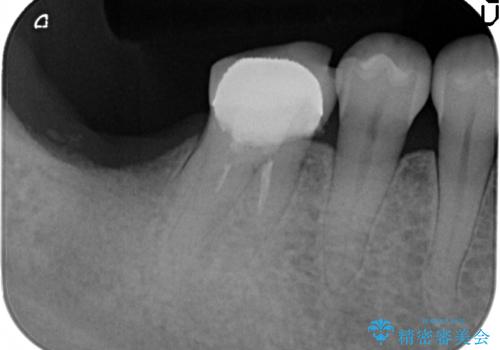

奥歯 インプラントによる機能回復

- 歯を欠損し、噛めないことの治療を希望され来院されました。

インプラントを用いて、しっかりとかめるような治療を計画します。

- 45万円(ストローマンインプラント・骨造成・チタンカスタムアバットメント・ジルコニアクラウン)費用は治療当時の料金となります

最後方臼歯はインプラントを用いることでしっかりと咬合機能を回復することができます。